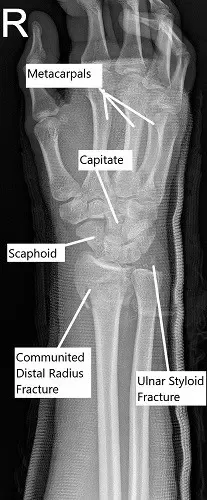

Radiografía de la muñeca en vista oblicua que muestra una fractura conminuta del radio distal.

En el examen físico, había hinchazón y sensibilidad en la muñeca derecha. El examen neurovascular distal de la mano derecha fue normal. La radiografía y la tomografía computarizada de la muñeca derecha revelaron una fractura conminuta del radio distal derecho, fractura del estiloides cubital y disrupción de la articulación radio-cubital distal (DRUJ). Ella tenía una reducción cerrada previa en urgencias que no era suficiente.